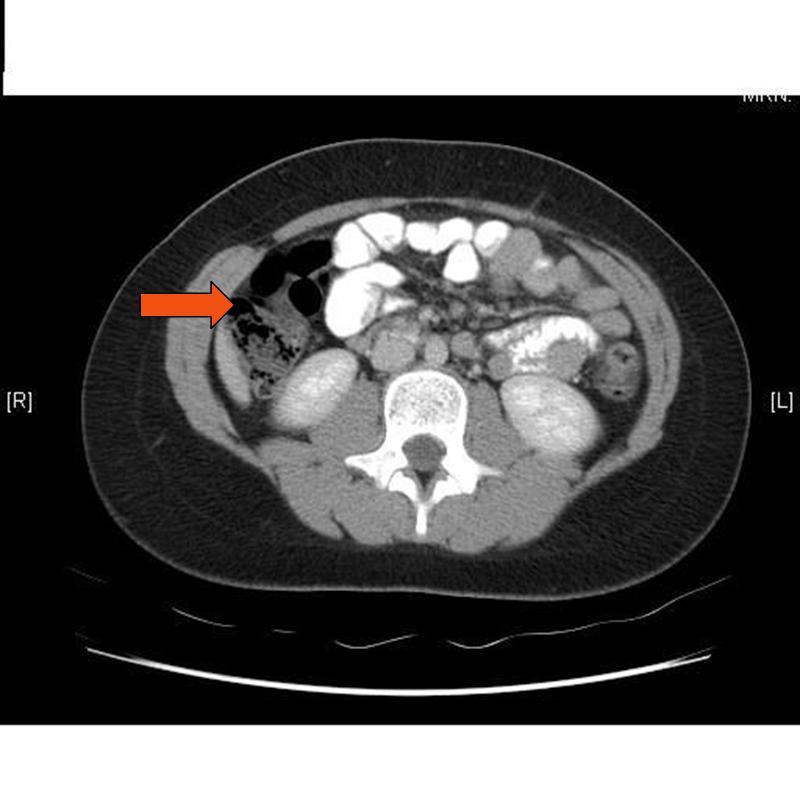

Teratoma ovárico complicado. En la TC con contraste en corte axial se ... 😈